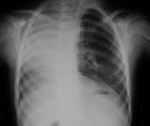

На рентгенограмме легких видно смещение средостения к больной стороне. В верхних отделах пораженного гемиторакса имеется участок нормальной ткани легкого, что может привести к ошибочному диагнозу. В целях дифференциальной диагностики этого дефекта с гидротораксом, ателектазом или диафрагмальной грыжей выполняется сканер грудной клетки. Контраст трахеобронхиального дерева во время бронхографии позволяет отличить легочную аплазию от агенеза. Ангиопульмонография выявляет отсутствие легочных сосудов.